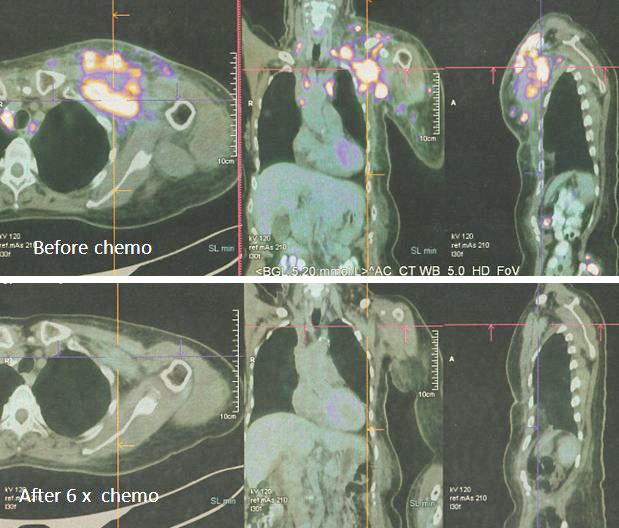

8. Pemindaian PET pada 14 April 2022 memang menunjukkan respon yang baik.

Sebelum kemo ———– setelah 6 siklus kemo

1. Temuan scan menunjukkan respon metabolik lengkap pada kekambuhan dinding dada, metastasis nodal dan penyebaran jauh.

2. Perubahan atelektasis baru pada dasar paru kiri dengan efusi pleura kiri ringan mungkin disebabkan oleh infeksi baru-baru ini.

1. Hasil kemoterapi yang luar biasa.

Bandingkan ketiga gambar ini :

Kiri: Setelah operasi Lucy menjalani terapi alternatif, menolak kemoterapi. Hasilnya adalah metastasis luas (tengah).

Kanan: Lucy tidak punya pilihan selain menjalani kemoterapi. Hasil dari 6 siklus kemoterapi sungguh luar biasa! Selama lebih dari 25 tahun saya berurusan dengan pasien kanker, saya belum pernah melihat hasil kemoterapi yang luar biasa seperti ini. Salut dengan ahli onkologi! Anda menyelamatkan Lucy!

Faktanya, hasil chemo ini sangat sulit dipercaya sehingga orang tergoda untuk bertanya apakah itu asli dan bukan palsu? Jawaban saya TIDAK, studi detail hasil PET scan di bawah ini adalah nyata! Kaji gambar berikut dengan cermat – sebelum dan sesudah kemoterapi.